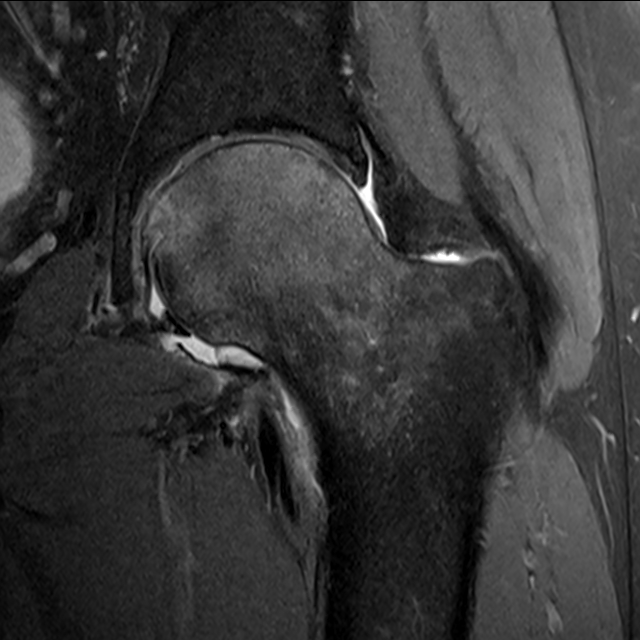

Transient Osteoporosis of the Hip

Note: characteristic sparing of medial femoral head and greater trochanter.